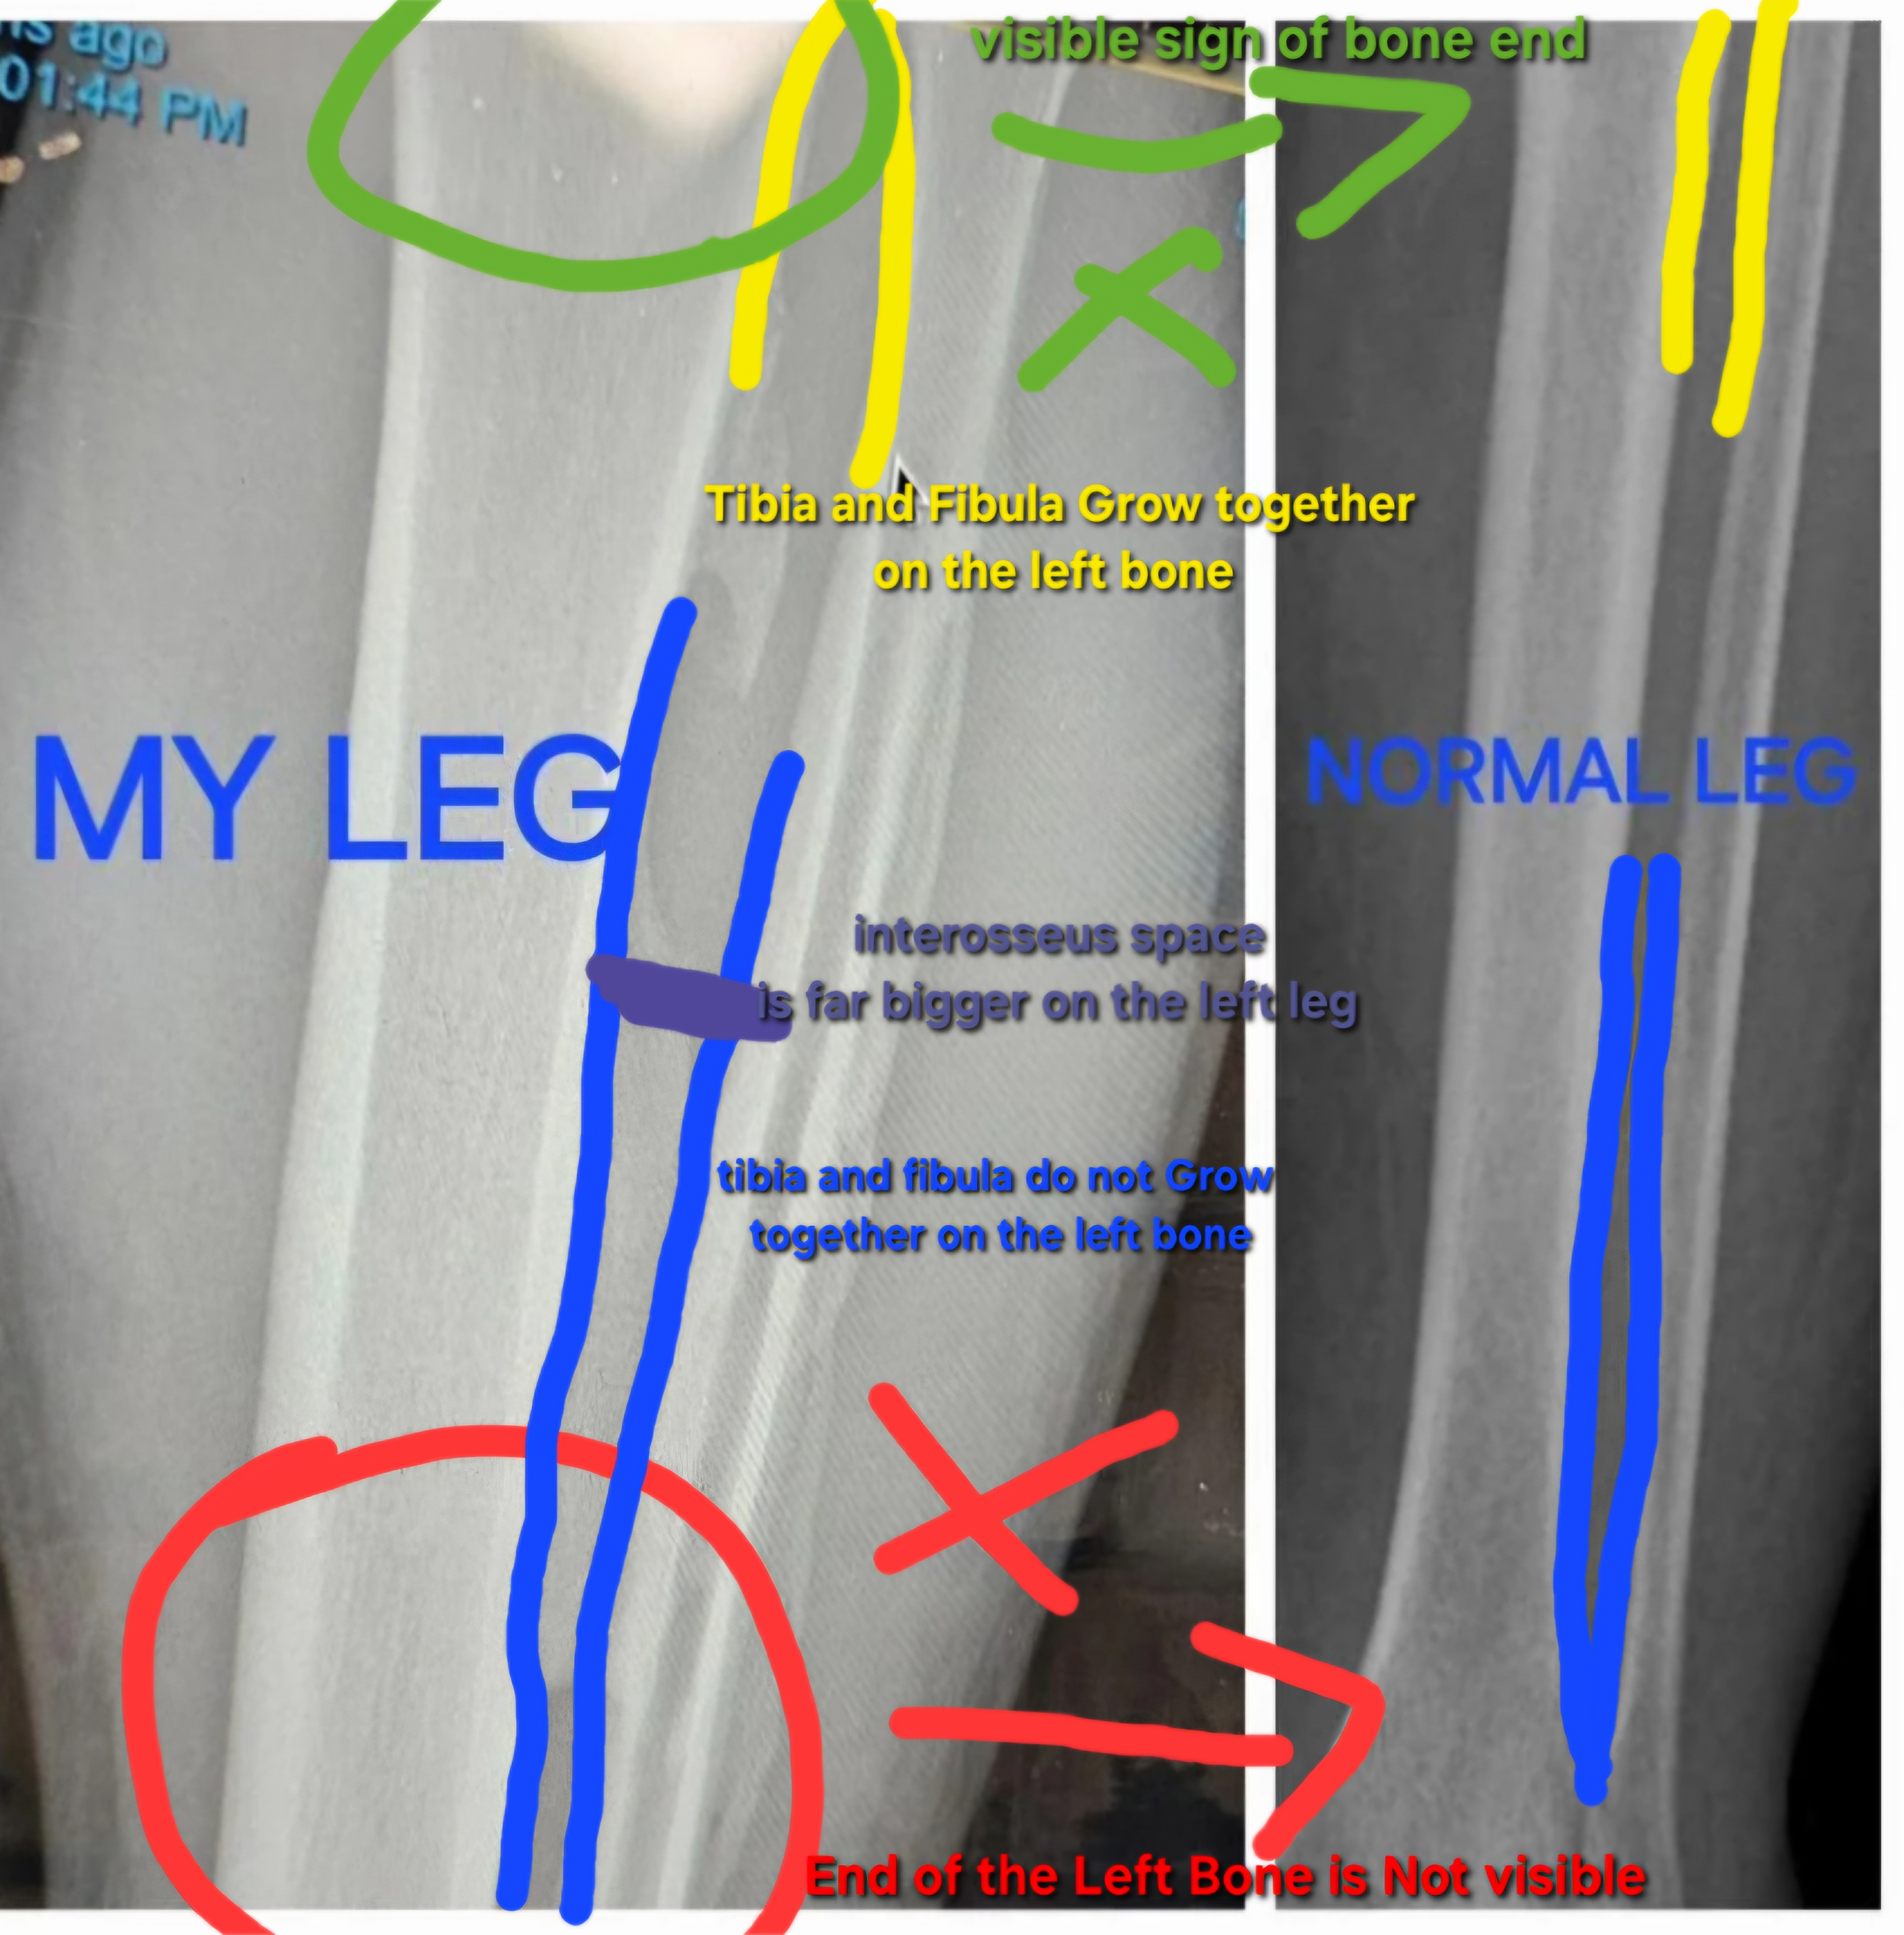

"my leg" "normal leg" (leg of someone else) And obviously the "my leg" is zoomed in, Like i said Bones is genetics and not everyond is the sameView attachment 5435

This is pretty obvious proof dude

The my leg isn’t zoomed in lmao. He has bigger bones due to constant damage/pressure. How many times do I have to say it before it gets through your skull you iqlet"my leg" "normal leg" (leg of someone else) And obviously the "my leg" is zoomed in, Like i said Bones is genetics and not everyond is the same

The picture I showed IS proof. U have showed none so far. Also I’m not even doing it through wolf’s law or some other bullshit. I’m doing through ossification of hematomasso many times until u find actual proof for your debunked claim

yo dumbass. The first picture isn’t zoomed in. And the second isn’t zoomed out. EVEN IF THEY WERE WHICH THEY ARENT Sean’s bone is still biggerYeah sure bro holdon ill make a closed in pic of the leg while the other one is zoomed out boom got you proof![]()

yo dumbass. The first picture isn’t zoomed in. And the second isn’t zoomed out. EVEN IF THEY WERE WHICH THEY ARENT Sean’s bone is still bigger